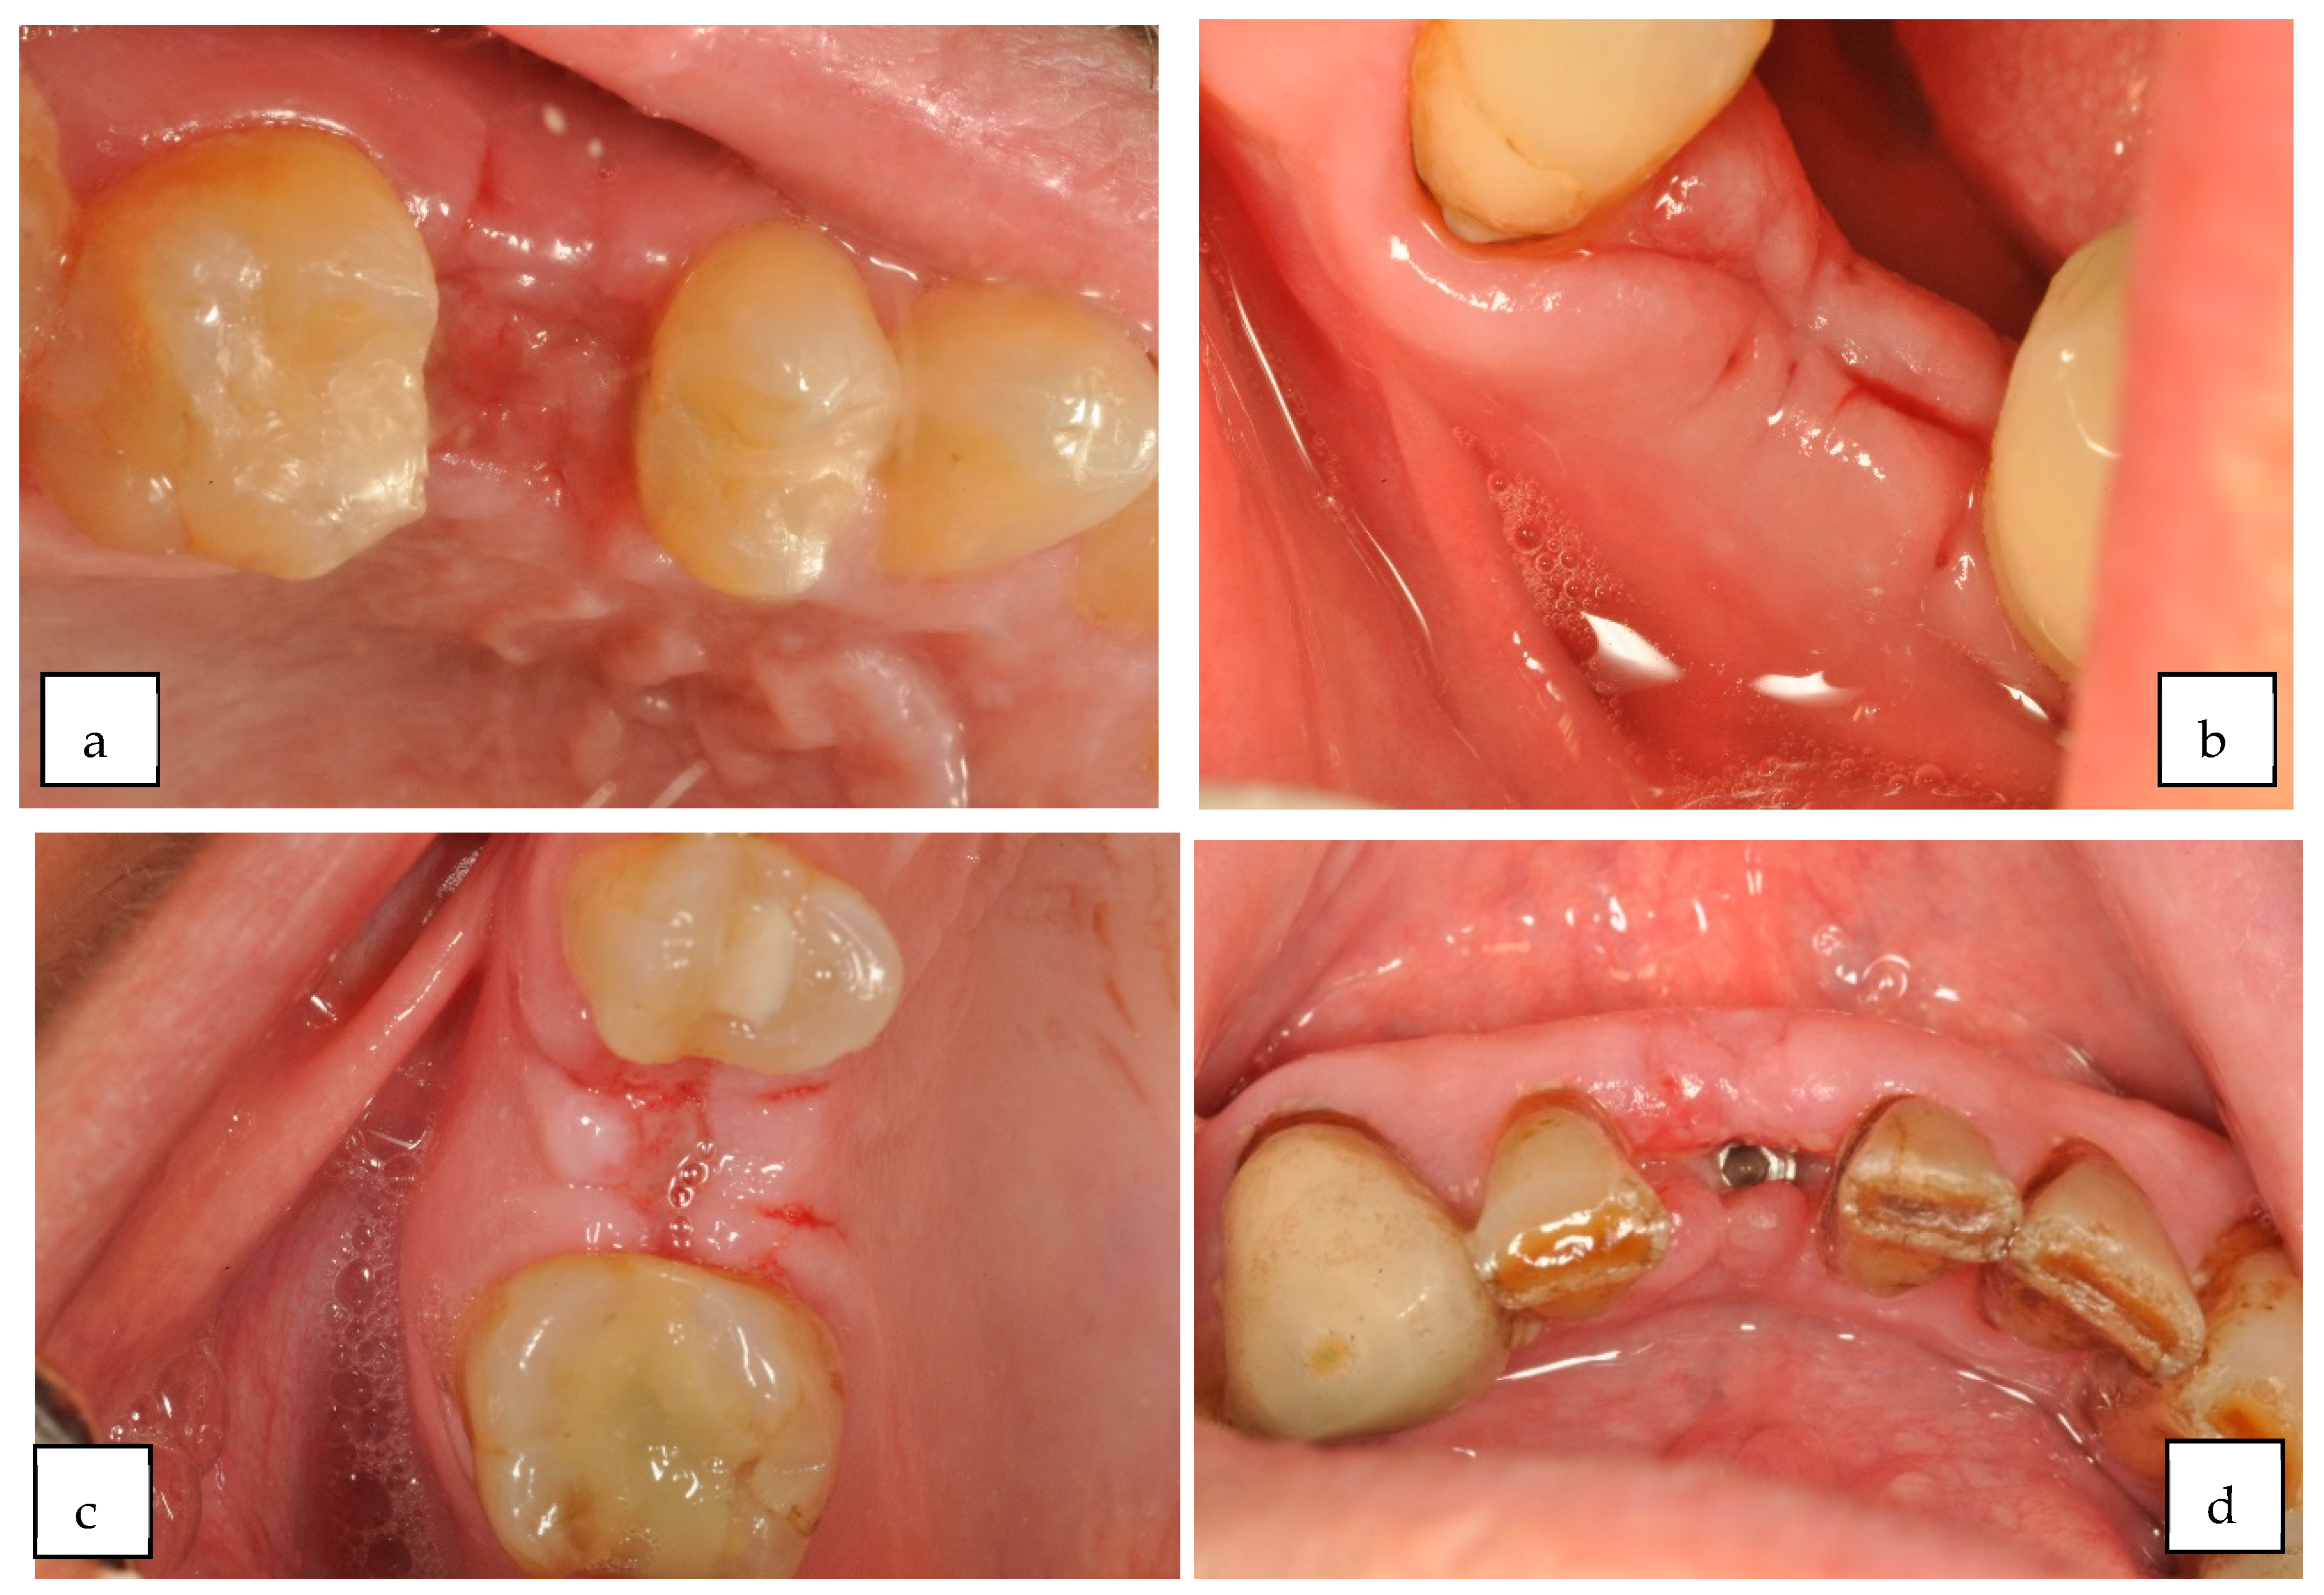

| Wachtel 2003 EHI 1–2 s | |

| Full closure |

| Incomplete closure |